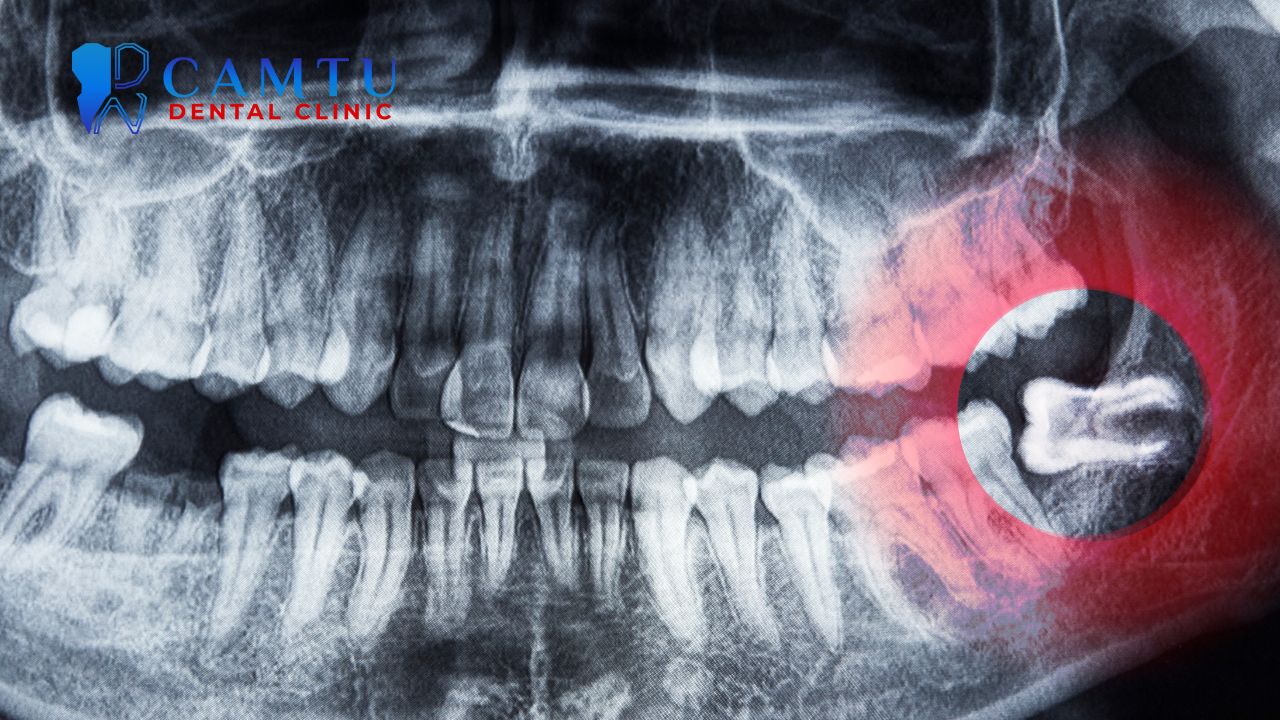

Nhổ răng khôn truyền thống là phương pháp được áp dụng phổ biến trong nha khoa. Trước khi thực hiện, bác sĩ sẽ chụp X-quang để xác định vị trí và hướng mọc của răng khôn. Sau đó, vùng nhổ được gây tê cục bộ để giảm đau. Bác sĩ tiến hành rạch nướu, loại bỏ xương nếu cần và chia nhỏ răng để lấy ra dễ dàng hơn.

Chụp X-quang hoặc phim CT giúp xác định chính xác vị trí, hướng mọc và mức độ ảnh hưởng của răng khôn. Đây là cơ sở quan trọng để bác sĩ đánh giá mức độ phức tạp của ca nhổ. Việc chẩn đoán đúng ngay từ đầu giúp tránh những can thiệp không cần thiết.